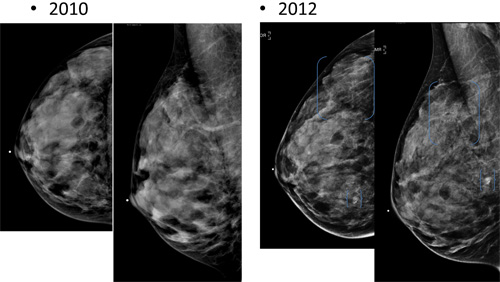

Routine screening mammography has traditionally been recommended by both the USPSTF and the American Cancer Society for all women over the age of 40. In 2009, the USPSTF issued controversial new guidelines recommending routine screening with mammography every two years for women 50 to 74 years old. In the studies being presented at RSNA 2012, researchers analyzed the impact of the new guidelines on women between the ages of 40 and 49 and the Medicare population.

For her study, Arleo and a team of researchers analyzed data on screening mammography at New York – Presbyterian Hospital — Weill Cornell Medical College between 2007 and 2010. Over the four years, 43,351 screening exams were performed, which led to the detection of 205 breast cancers.

Of the women screened in the study, 14,528, or 33.5 percent, were between the ages of 40 and 49. Of the 205 breast cancers detected, 39 (19 percent) were found in the 40-49 age group. Of those cancers, more than 50 percent (21 of 39) were invasive. Only three of the women between the ages of 40 and 49 diagnosed with cancer had a first-degree relative with pre-menopausal cancer.